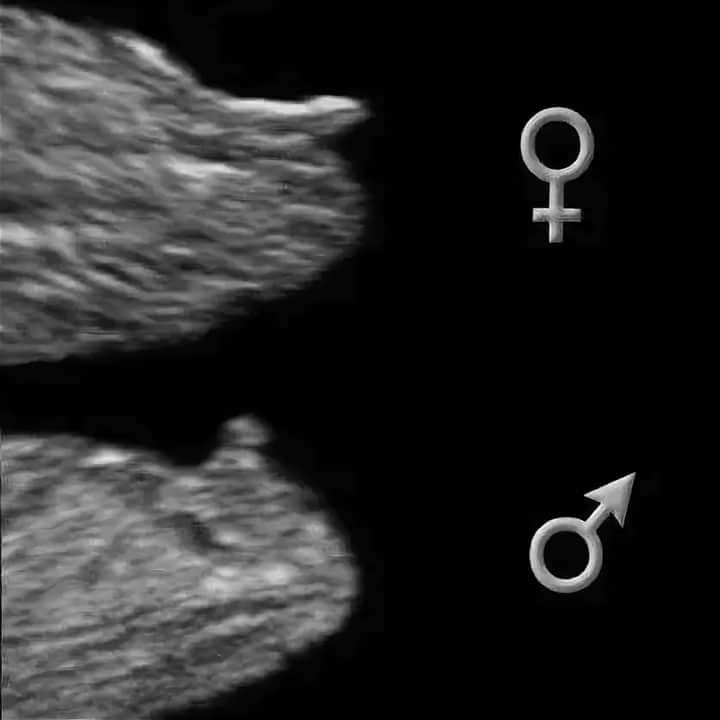

По мнению врача у нас девочка😍

А вы кого видите?) смотрела в интернете, что по наклону бугорка определяют)